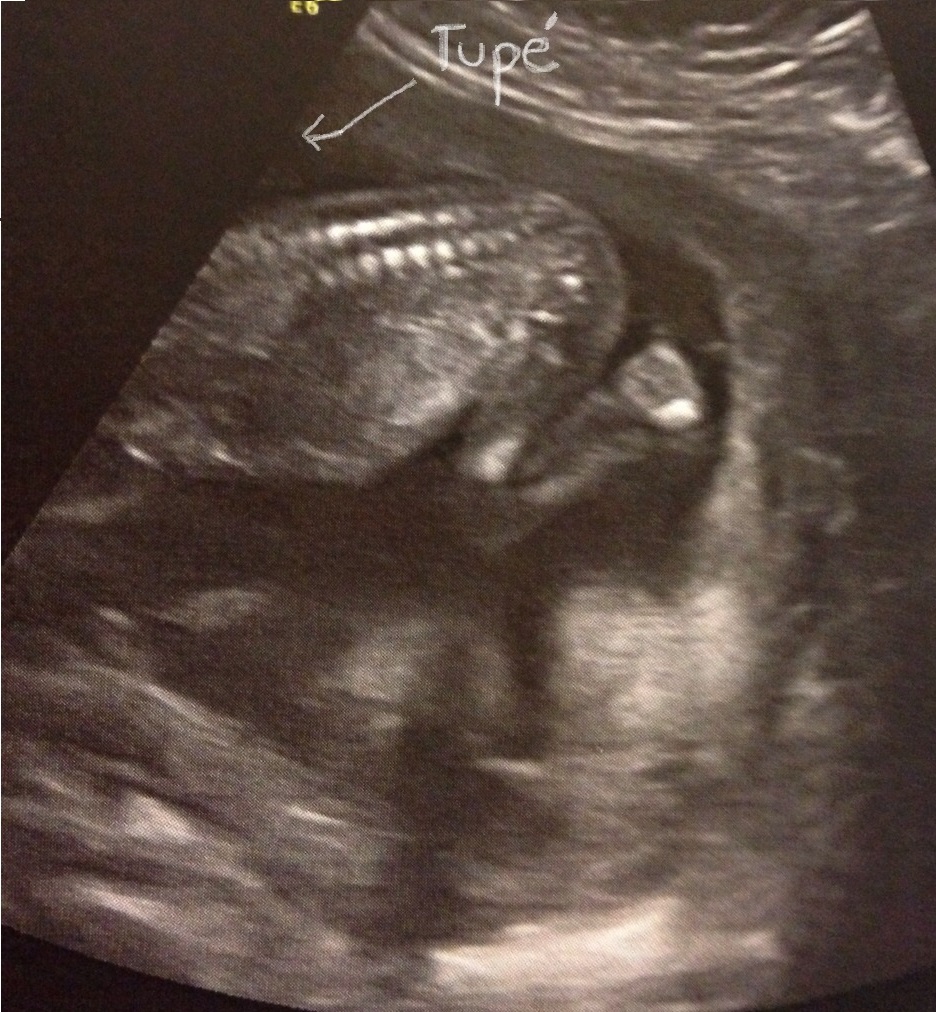

Pero nada que no se pueda solucionar viendo el culo de tu pequeño cigoto:

la foto

Besis.

#UnaJamelgaIsComing… #CigotoEsquéletor #CachorroBalashunta #NoSinMiHija  #PequeñoAlfajor